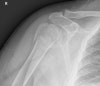

X-ray : 상완골 근위부 골절(Proximal humerus fracture)